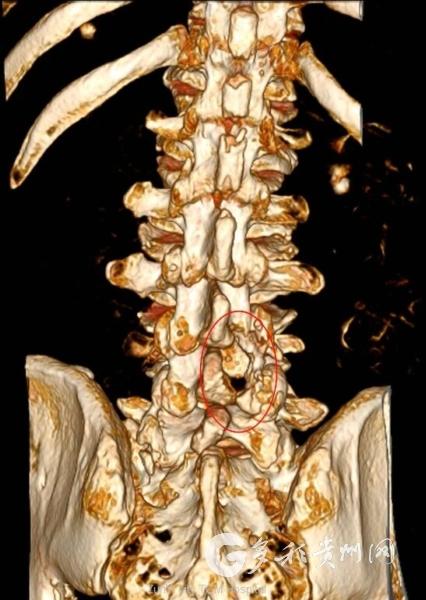

经腰椎CT及MRI搜检明确会诊为腰4/5椎间盘脱出、黄韧带肥厚、继发严重椎管狭隘。患者年龄已高,归并高血压、糖尿病、冠心病、慢性羁系性肺疾病、慢性心衰等多种基础疾病,通例开适度术风险较高。经充分疏导,患者及家属明确条款微创诊疗。

手术仅作念约2.5cm细小切口,开云sports通过枢纽镜援救单通谈内镜,在高清视线下精确操作,不剥离肌肉、不碎裂韧带与枢纽结构,术中出血少许,最猛流程保护脊柱巩固性。团队精确摘除脱出椎间盘组织与增厚黄韧带,充分松解受压神经根,全程可视化操作将神经毁感冒险降至最低。